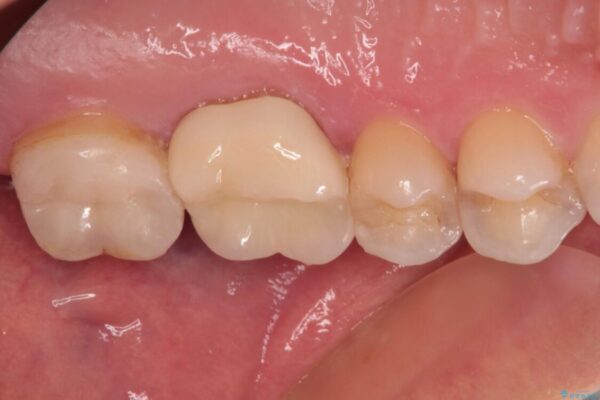

強い咬合力を負担する第一大臼歯であるため、根管治療後は速やかにオールセラミッククラウンにて補綴治療を行うこととしました。

初診時は神経組織の生活反応が認められましたが、2日後に処置を行ったときには、既に反応はなくなっている状態でした。

神経組織は壊死が始まっておりましたが、初回処置後には痛みを感じることもなくなり、2回目に無事に根管治療を終えることができました。

治療後

• 奥歯がズキズキと痛む 奥歯の虫歯治療 治療後画像